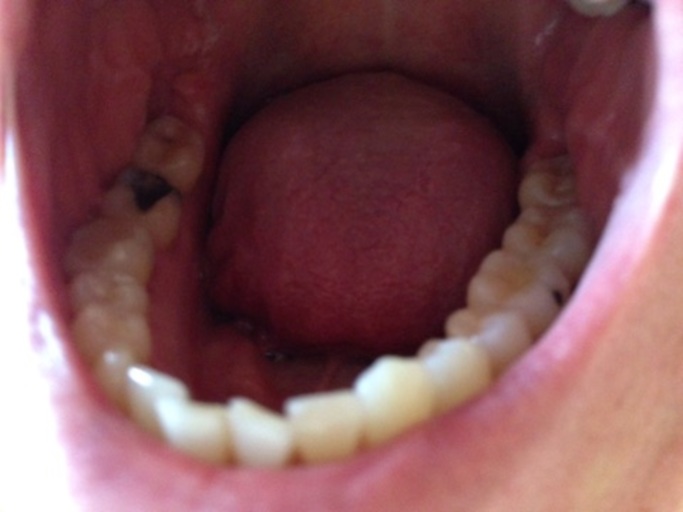

Is the hole in my tooth a cavity or broken composite filling?

Hello, I have a question about my back molar on the bottom row. I have had white composite fillings as well as sealants in the past years ago. It appears I have a hole in my tooth and it looks as though the filling has broken leaving a nice sized...